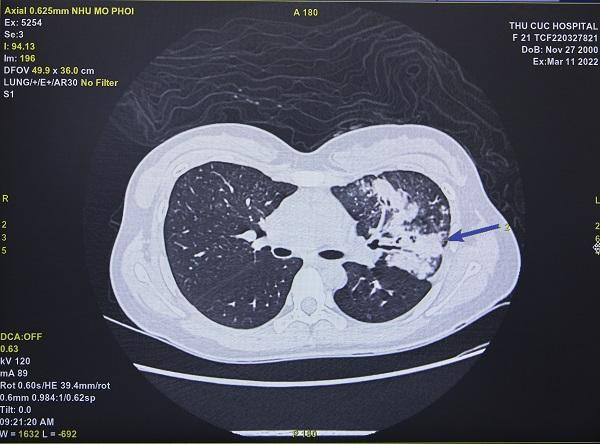

Chị N.T.T.T đã điều trị khỏi Covid-19 được 2 tuần, đến Bệnh viện Đa khoa Quốc tế Thu Cúc khám với triệu chứng tức ngực, khó thở kéo dài và thỉnh thoảng có ho. Sau khi khám với bác sĩ chuyên khoa, chị T. được chỉ định chụp cắt lớp vi tính phổi để chẩn đoán tình trạng tổn thương phổi. Kết quả chẩn đoán ảnh cho thấy, nhu mô phổi bị tổn thương, xuất hiện viêm phổi và có các tổn thương dạng kính mờ sau nhiễm virus Sars-CoV-2.

| Hình ảnh phổi của bệnh nhân T. bị tổn thương sau nhiễm virus Sars-CoV-2 (Ảnh: Thu Cúc TCI) |

Bác sĩ Nguyễn Quang Hanh - Trưởng khoa Chẩn đoán hình ảnh Bệnh viện ĐKQT Thu Cúc cho biết: “Trường hợp này người bệnh được chẩn đoán là viêm phổi sau nhiễm Covid-19. Rất may bệnh nhân khi có triệu chứng đã đi khám sớm nên phổi bị tổn thương không quá nghiêm trọng. Bác sĩ điều trị sẽ lên phác đồ để phục hồi các nhu mô phổi bị tổn thương cho bệnh nhân, tránh tình trạng xơ phổi sau này”.